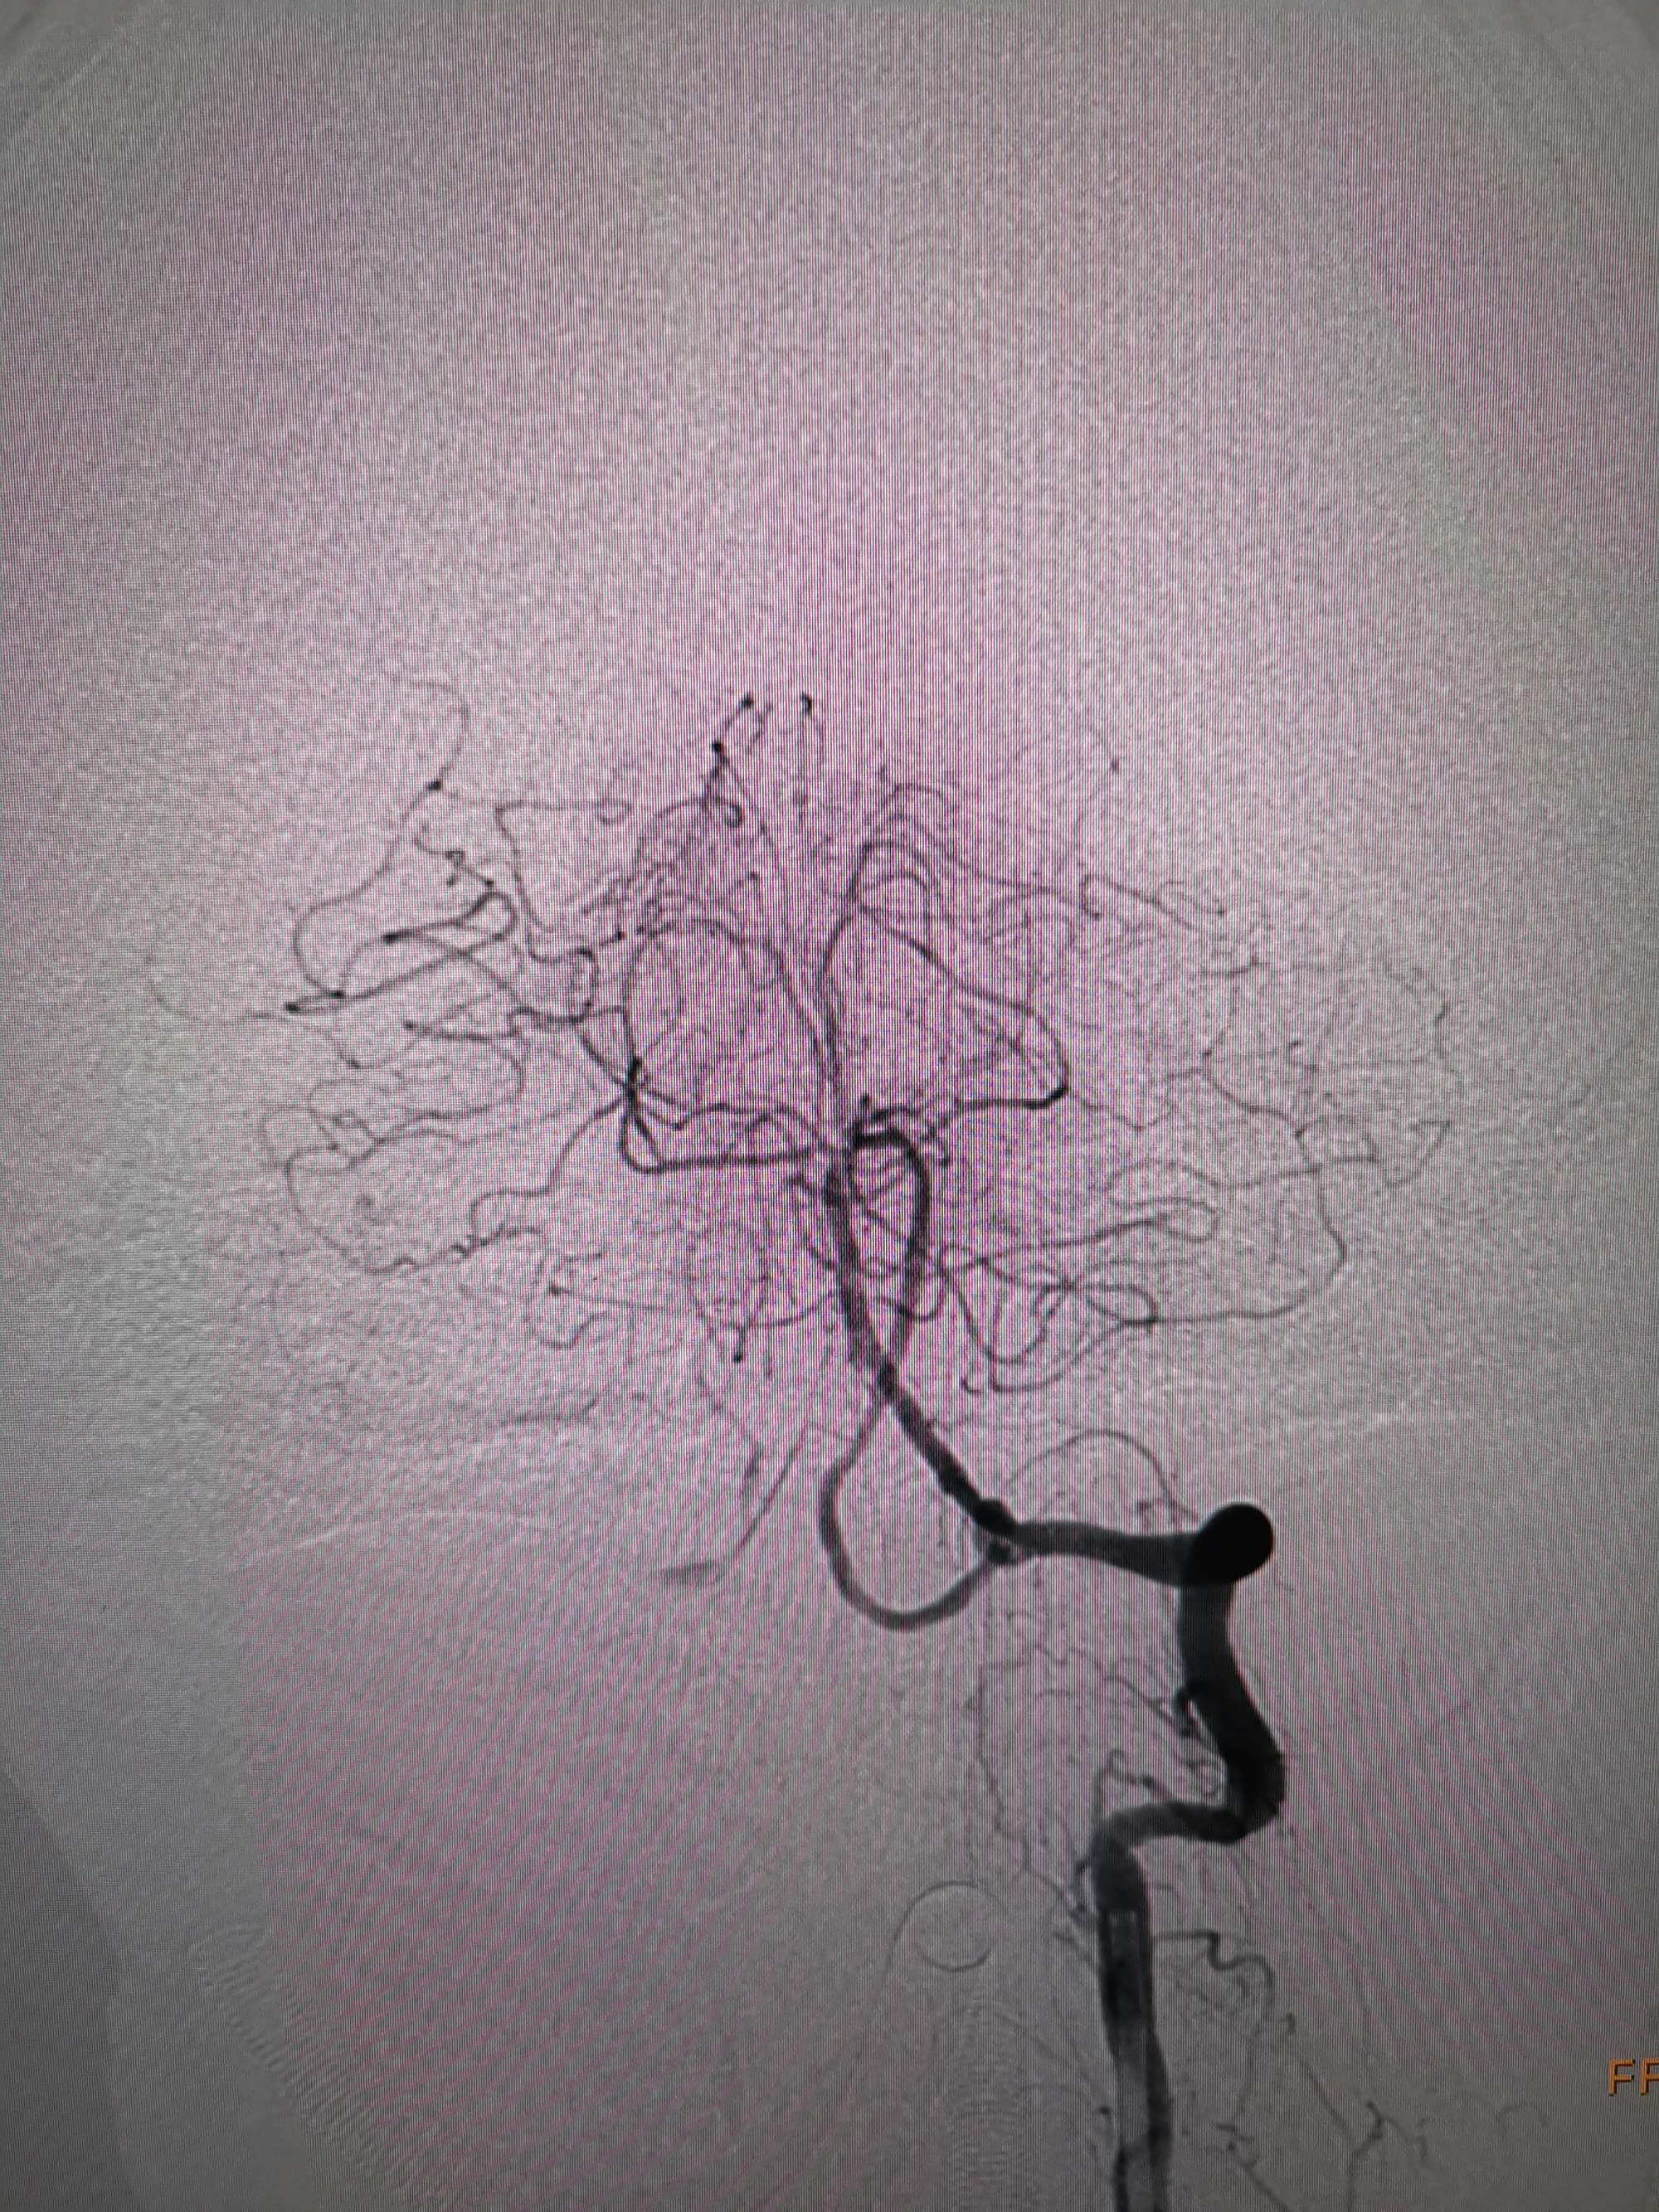

在微导管支撑下先将微导丝和微导管穿过闭塞段,微导管超选造影证实位于基底动脉真腔后更换300cm外周交换导丝,撤出微导管后按从小到大,从远到近的原则行球囊扩张,本例手术选择了1.5✖️15、2.0✖️20、2.5✖️20球囊进行扩张,扩张满意后植入Enterprise支架,手术结束。

术后造影见左侧椎动脉闭塞段管腔恢复正常直径,远端血运良好。